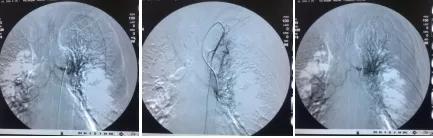

1个月后张爷爷来院复诊,复查胸部CT提示:左肺上叶肿块缩小到1cm,肺不张明显缓解,胸腔积液减少 。 张爷爷表示近1月来状态明显好转,未再咯血,活动也不像之前那样一动就喘,平时走路吃饭都不影响。入院后PS评分1分,临床疗效评估为PR。 为更好的控制肿瘤,进行了第二次介入治疗。 行支气管动脉及胸廓内动脉造影后显示肿瘤染色明显减少,继续灌注化疗药物后,将肿瘤滋养动脉进行了彻底栓塞。 术后无不适, 顺利完成第二次治疗。

第一次介入造影显示肿瘤供血动脉及肿瘤染色

第二次介入造影显示肿瘤供血动脉减少及肿瘤染色明显减轻